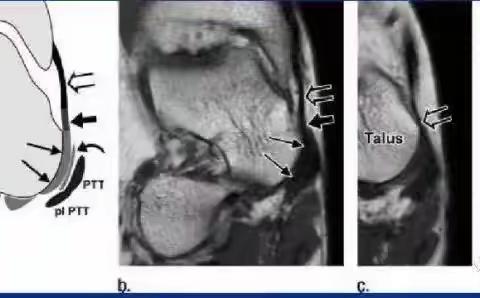

影像解剖学笔记

2023-09-23 255阅读